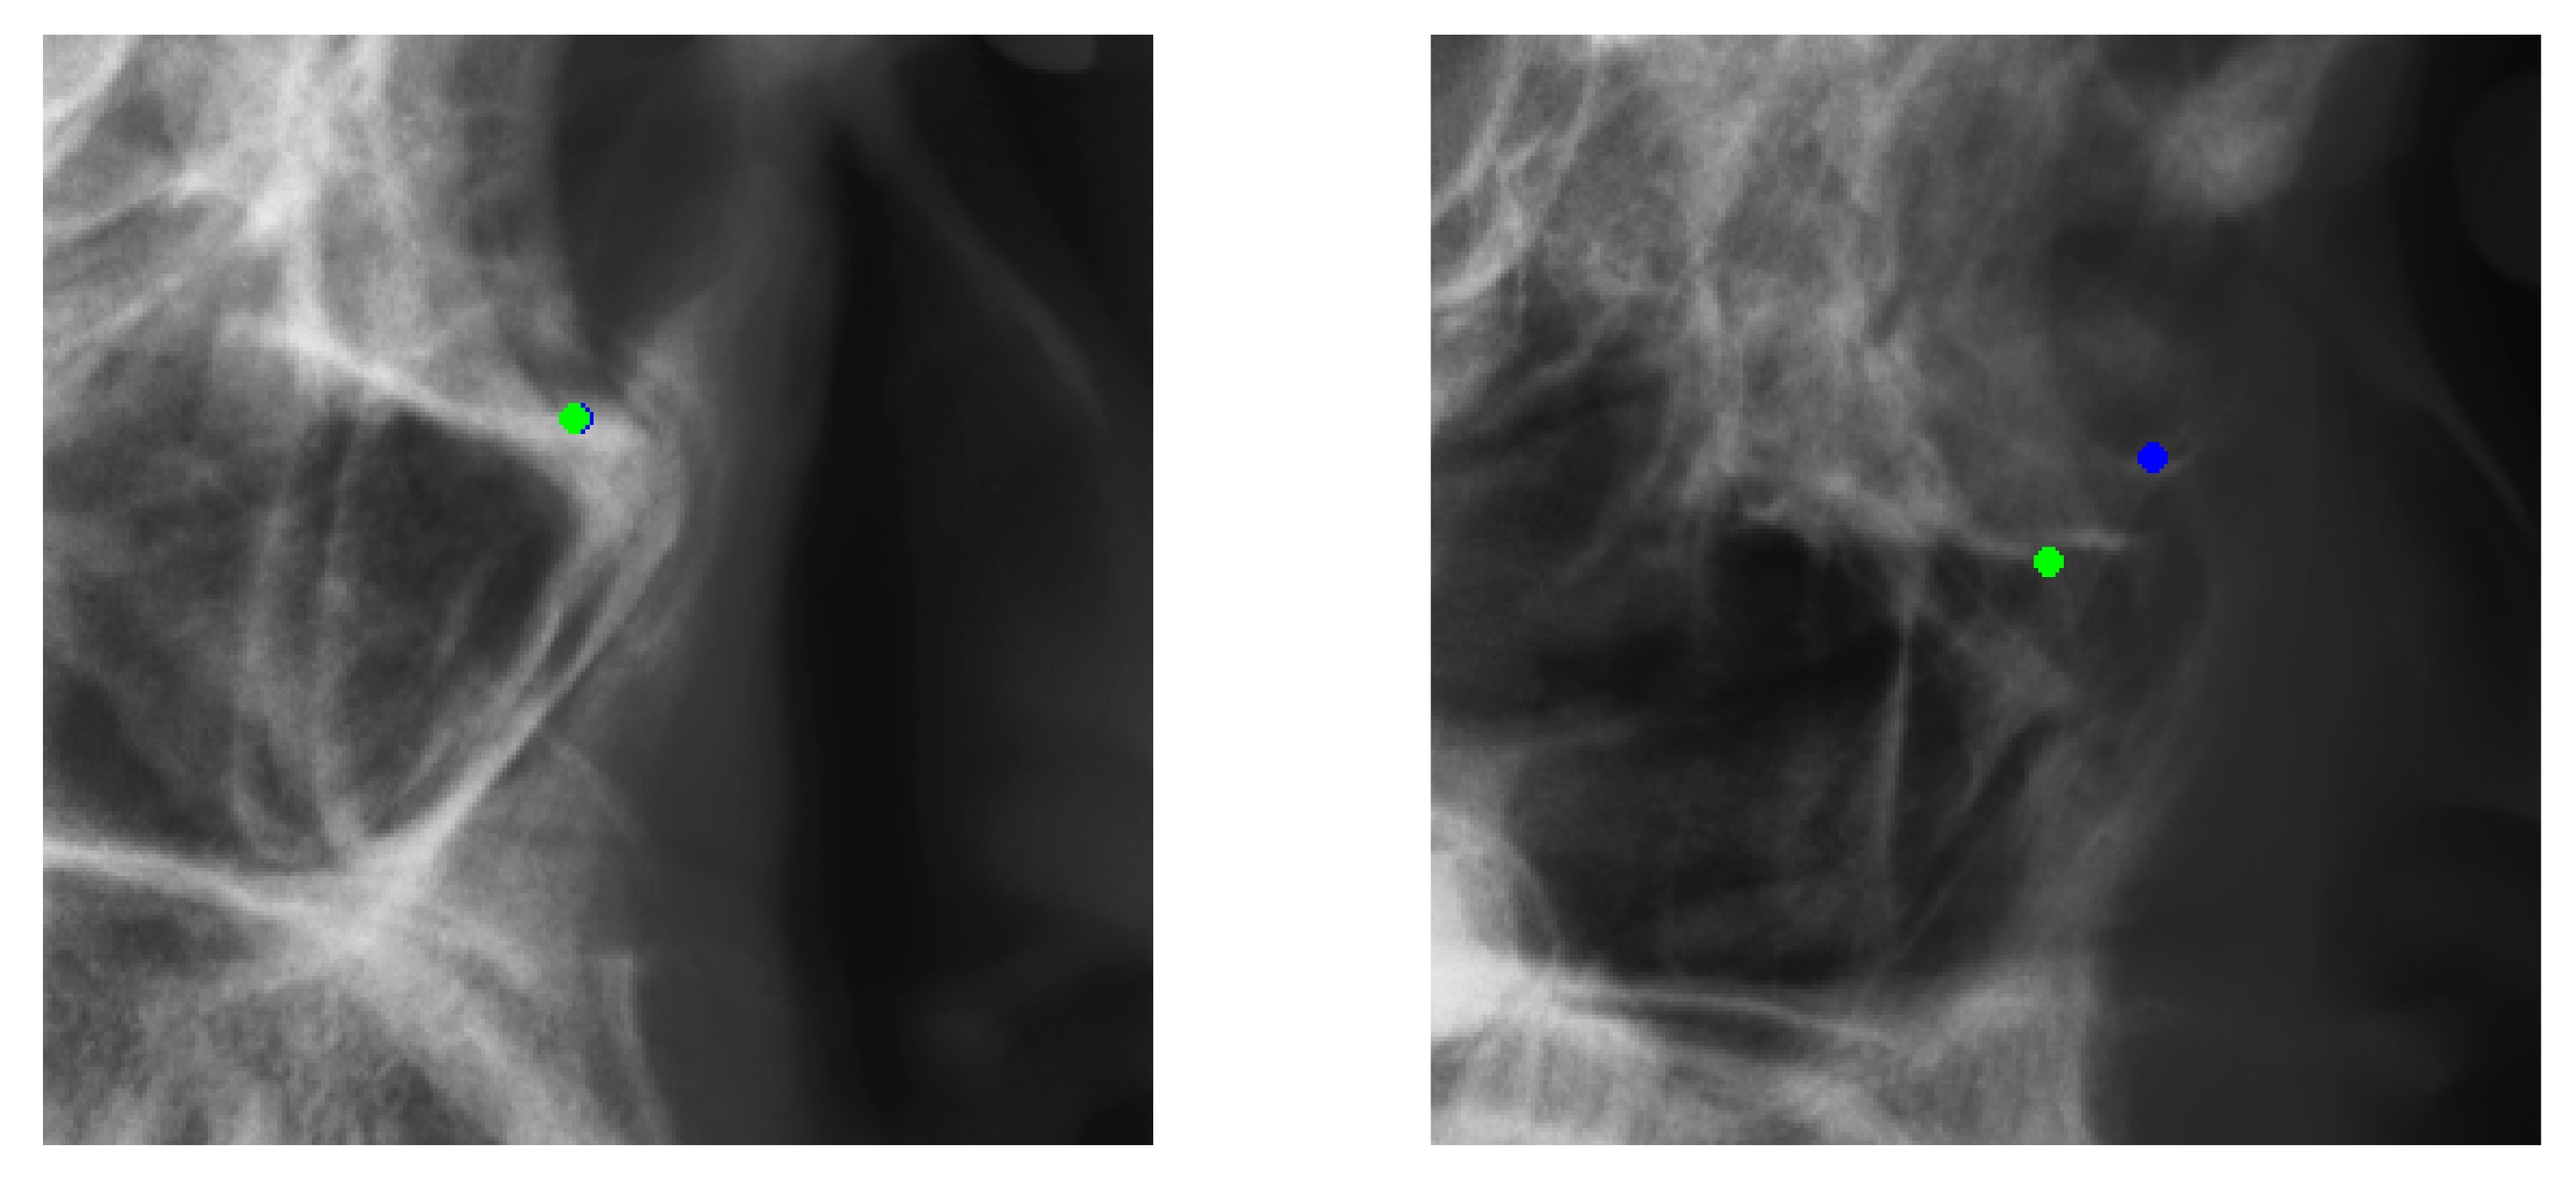

Figure 10. Successful detection example from Testset1 and failed detection example from Testset2 on Landmark 3. Green points: predicted result. Blue points: ground-truth location.